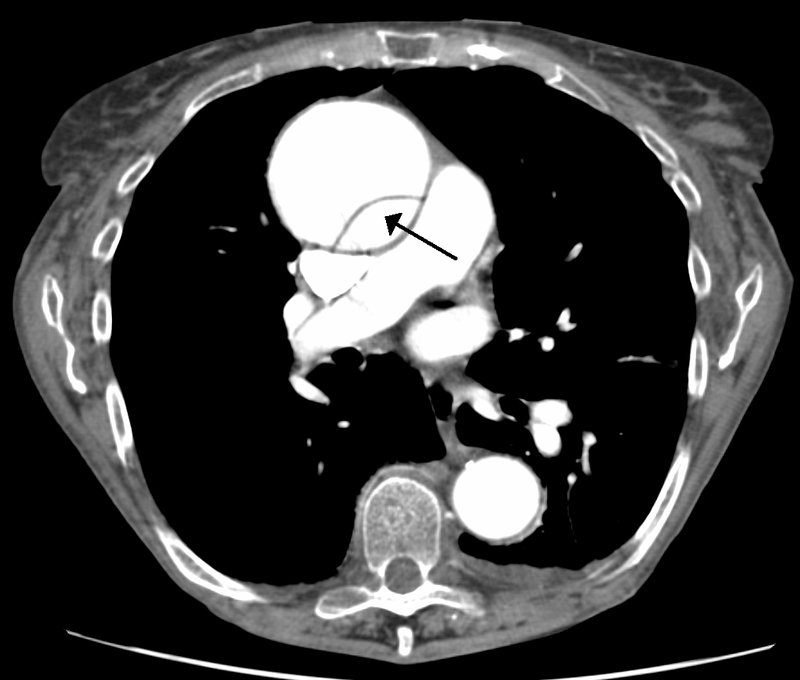

Abdominal Aortic Aneurysm

Abdominal aortic aneurysm (AAA) is an aneurysm of the abdominal aorta.

Abdominal aortic aneurysm typically develops above the aortic bifurcation but below the renal arteries.

Abdominal aortic aneurysm (AAA) is typically associated with hypertension and atherosclerosis.

Risk factors for abdominal aortic aneurysm (AAA) include:

- Male sex

- Smoking

- Elderly

- Atherosclerosis

- Hypertension

Atherosclerosis causes the vessel wall to atrophy and become weaker by raising the diffusion barrier to the media.

Abdominal aortic aneurysm (AAA) typically presents with a triad of:

- Flank pain

- Pulsating abdominal mass

- Hypotension

Symptoms of abdominal aortic aneurysm include an abdomen lump that pulses initially and enlarges over time.

Complications of abdominal aortic aneurysm (AAA) include:

- Rupture, especially when the diameter is greater than 5 cm

- Compression of nearby structures (such as the ureter)

- Thrombosis

- Embolism